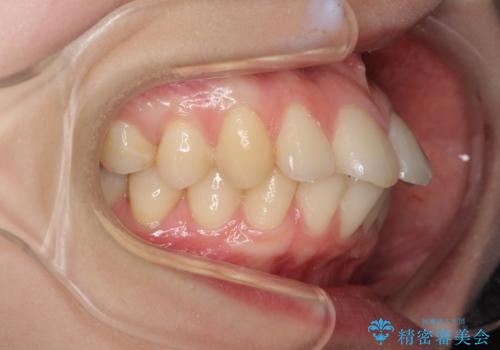

- 口元の突出感と口の閉じにくさを気にして来院された患者様です。

上下左右第一小臼歯4本を抜歯し、ワイヤー装置にて口元を引っ込めるよう矯正治療を行うこととしました。

ご友人などがびっくりするほど口元の突出感を改善することができ、患者様には大変満足していただきました。